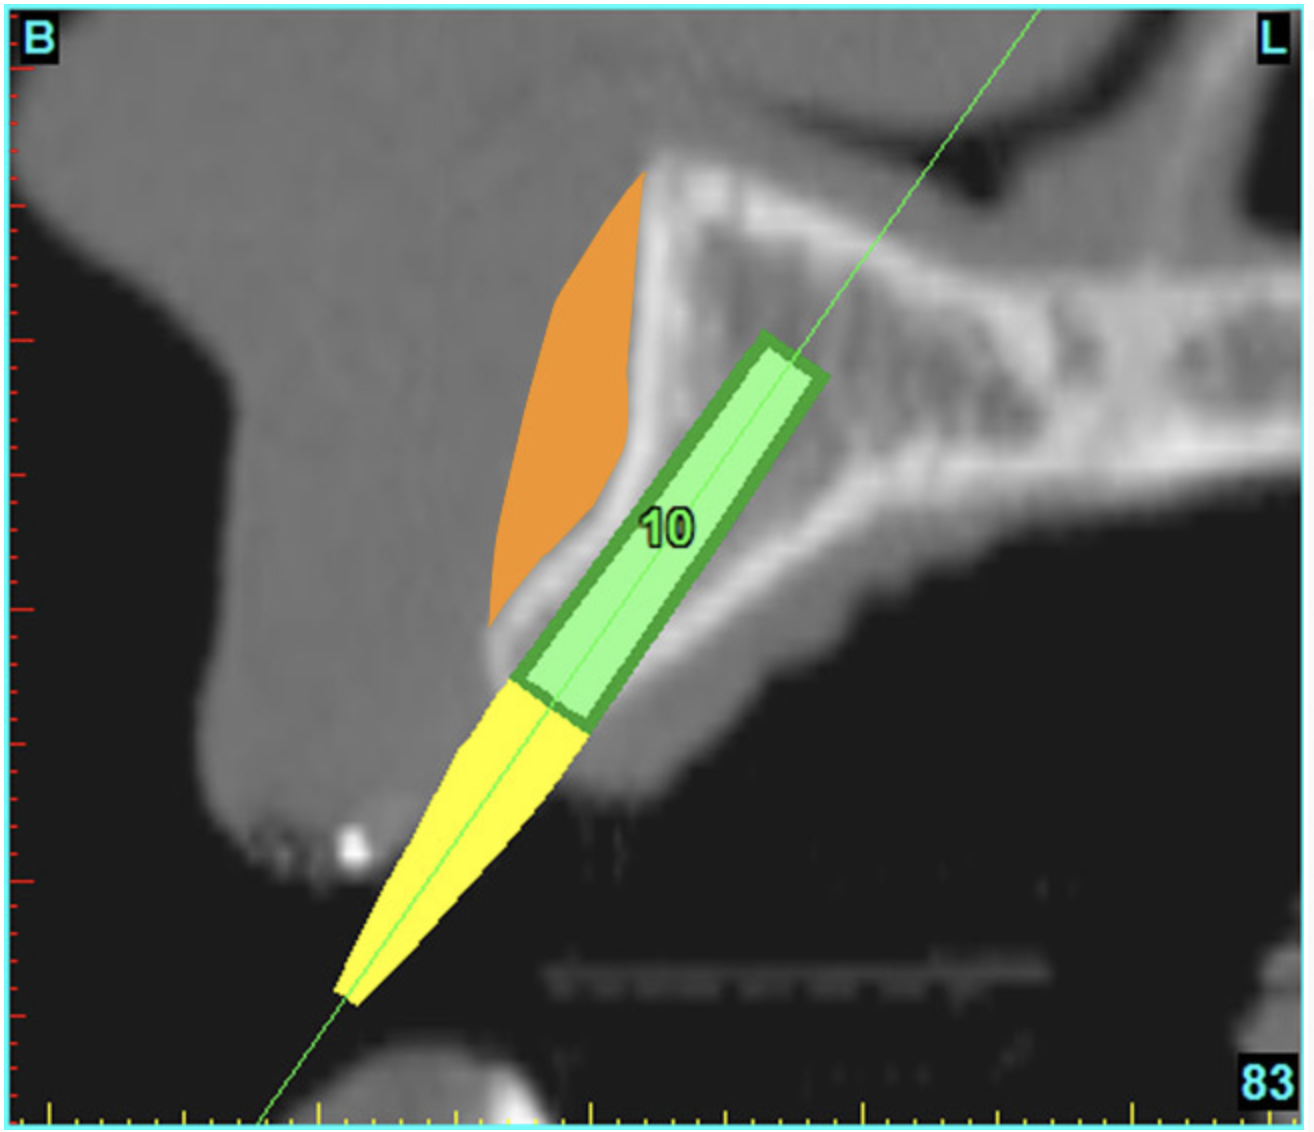

After the basic plan had been established, it was re-evaluated using interactive 3D images. The reconstructed 3D view of the maxilla clearly illustrated the extent of the bilateral facial concavities, and the root eminences of the adjacent and posterior teeth (Figure 7A). The placement of the virtual implants then was evaluated to ensure that the facial cortical plate was not perforated (Figure 7B). The implants were labeled individually as “7” and “10,” with the simulated yellow abutment projection indicating the facial-lingual inclination through the bone to the level above the incisal edge of adjacent teeth. The ability to gain a better understanding of these individual root forms can not be underestimated. The dental literature has suggested certain parameters for placing implants near teeth and implants next to other implants. However, there is little scientific 3D documentation to support these suggested rules.5-10 The use of an interactive treatment-planning software application permits closer scrutiny of previously difficult-to-visualize areas, and can now be used to redefine perceptions of spatial positioning of implants, especially when in close proximity to natural tooth roots, vital anatomy, and adjacent implants.27-29

Using different masking (segmentation) and threshold Hounsfield unit values, several new 3D bone volumes can be created which offer invaluable information. To help determine the final position of each implant a new bone model was created with a Hounsfield unit value of 1480, which eliminated all but the densest objects included in the scan data. (Results may vary depending on the CBCT machine used.) The inner and outer layers of bone were removed, leaving the underlying enamel and root structure of the teeth (Figure 8A). After the bone had been stripped away, the root inclinations were examined closely. The most striking findings confirmed the rotated position of the right central, while revealing the slight mesial dilaceration of the root apex, which converged on the space needed for the path of the potential implant (Figure 8B). The schematic shapes of the proposed implants were visualized for the right and left lateral spaces in different rotations of the 3D maxillary arch. It was at this point that a determination was made as to the appropriate implant shape and type that would fit the available space while avoiding encroachment on adjacent tooth roots. A tapered design implant (Tapered Screw-Vent®, Zimmer Dental, www.zimmerdental.com) was chosen from the large virtual library. With the SIMPlant software, the virtual library contains data from dozens of implant manufacturers and realistic computer-aided design representations as seen in Figure 9A through the translucent bone. The position of the left implant can be visualized with adequate mesial-distal distance between adjacent tooth roots (Figure 9B) and a more delicate placement (Figure 9C).

Figure 7a  The 3D reconstruction showed (A) the facial concavities and root eminences, and allowed (B) for evaluation of virtual implant placement to ensure the facial cortical plate was not perforated.

Figure 7b  The 3D reconstruction showed (A) the facial concavities and root eminences, and allowed (B) for evaluation of virtual implant placement to ensure the facial cortical plate was not perforated.

Figure 7b